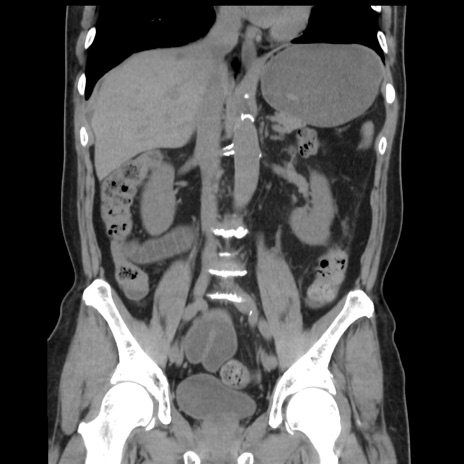

症例16(冠状断像)

【症例】 70歳代男性

【主訴】 腹痛、嘔吐

【現病歴】 約1ヶ月前より間欠的に腹痛と嘔吐あり、当院消化器内科を受診したところCTで多発する肝臓のLDAを指摘され、精査中であった。以降は消化器症状は安定していたが、2日前より嘔気と腹痛があり、同日より排便・排ガスが消失した。改善認めず、 本日、救急外来を受診した。

【既往歴】 大腸ポリープ切除後。

【身体所見】意識清明・会話良好、BT 36.3℃、BP 127/80mmHg、 P 80bpm、腹部:膨満あり、平坦・軟、上腹部正中および下腹部正中に圧痛あり、反跳痛なし、筋性防御なし。

【データ】WBC 7200、CRP 0.77